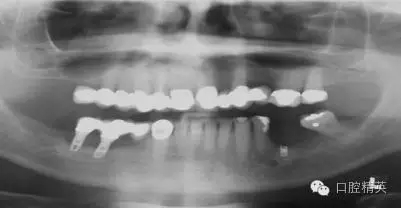

我們通過文獻(xiàn)和網(wǎng)站檢索獲得了一些關(guān)于種植體失敗的研究和綜述文章。一個(gè)和僅使用兩維放射診斷(根尖片或曲斷片)有關(guān)的常見失敗是上頜竇穿孔。(圖1a-c)通常牙醫(yī)由于錯(cuò)誤的估計(jì)了上頜竇底骨量高度而造成幾個(gè)毫米的上頜竇底穿孔。一些病例可能沒有癥狀,象圖中所示的這個(gè)病例,患者需要嚴(yán)格的監(jiān)控、復(fù)查。有些病例則出現(xiàn)并發(fā)癥,種植體不得不取出。

另一個(gè)和醫(yī)生僅用兩維放射線檢查造成的特殊并發(fā)癥是種植體進(jìn)入上頜竇。(圖2a-c)可能成為上頜竇異物的有牙齒,牙根,印模材料,牙科器械,近年來又增加了一個(gè)—種植體??上攵瑥纳项M竇中取出異物對(duì)患者來講是創(chuàng)傷很大的。

其他研究也報(bào)道過,對(duì)于這種病例,唯一的選擇是用根管顯微鏡或Caldwell Luc技術(shù)從上頜竇中取出種植體。有些文章報(bào)道了如何處理進(jìn)入上頜竇的種植體,但很少?gòu)念A(yù)防的角度來談這個(gè)問題,其實(shí)很簡(jiǎn)單,術(shù)前應(yīng)該應(yīng)用CBCT成像檢查。